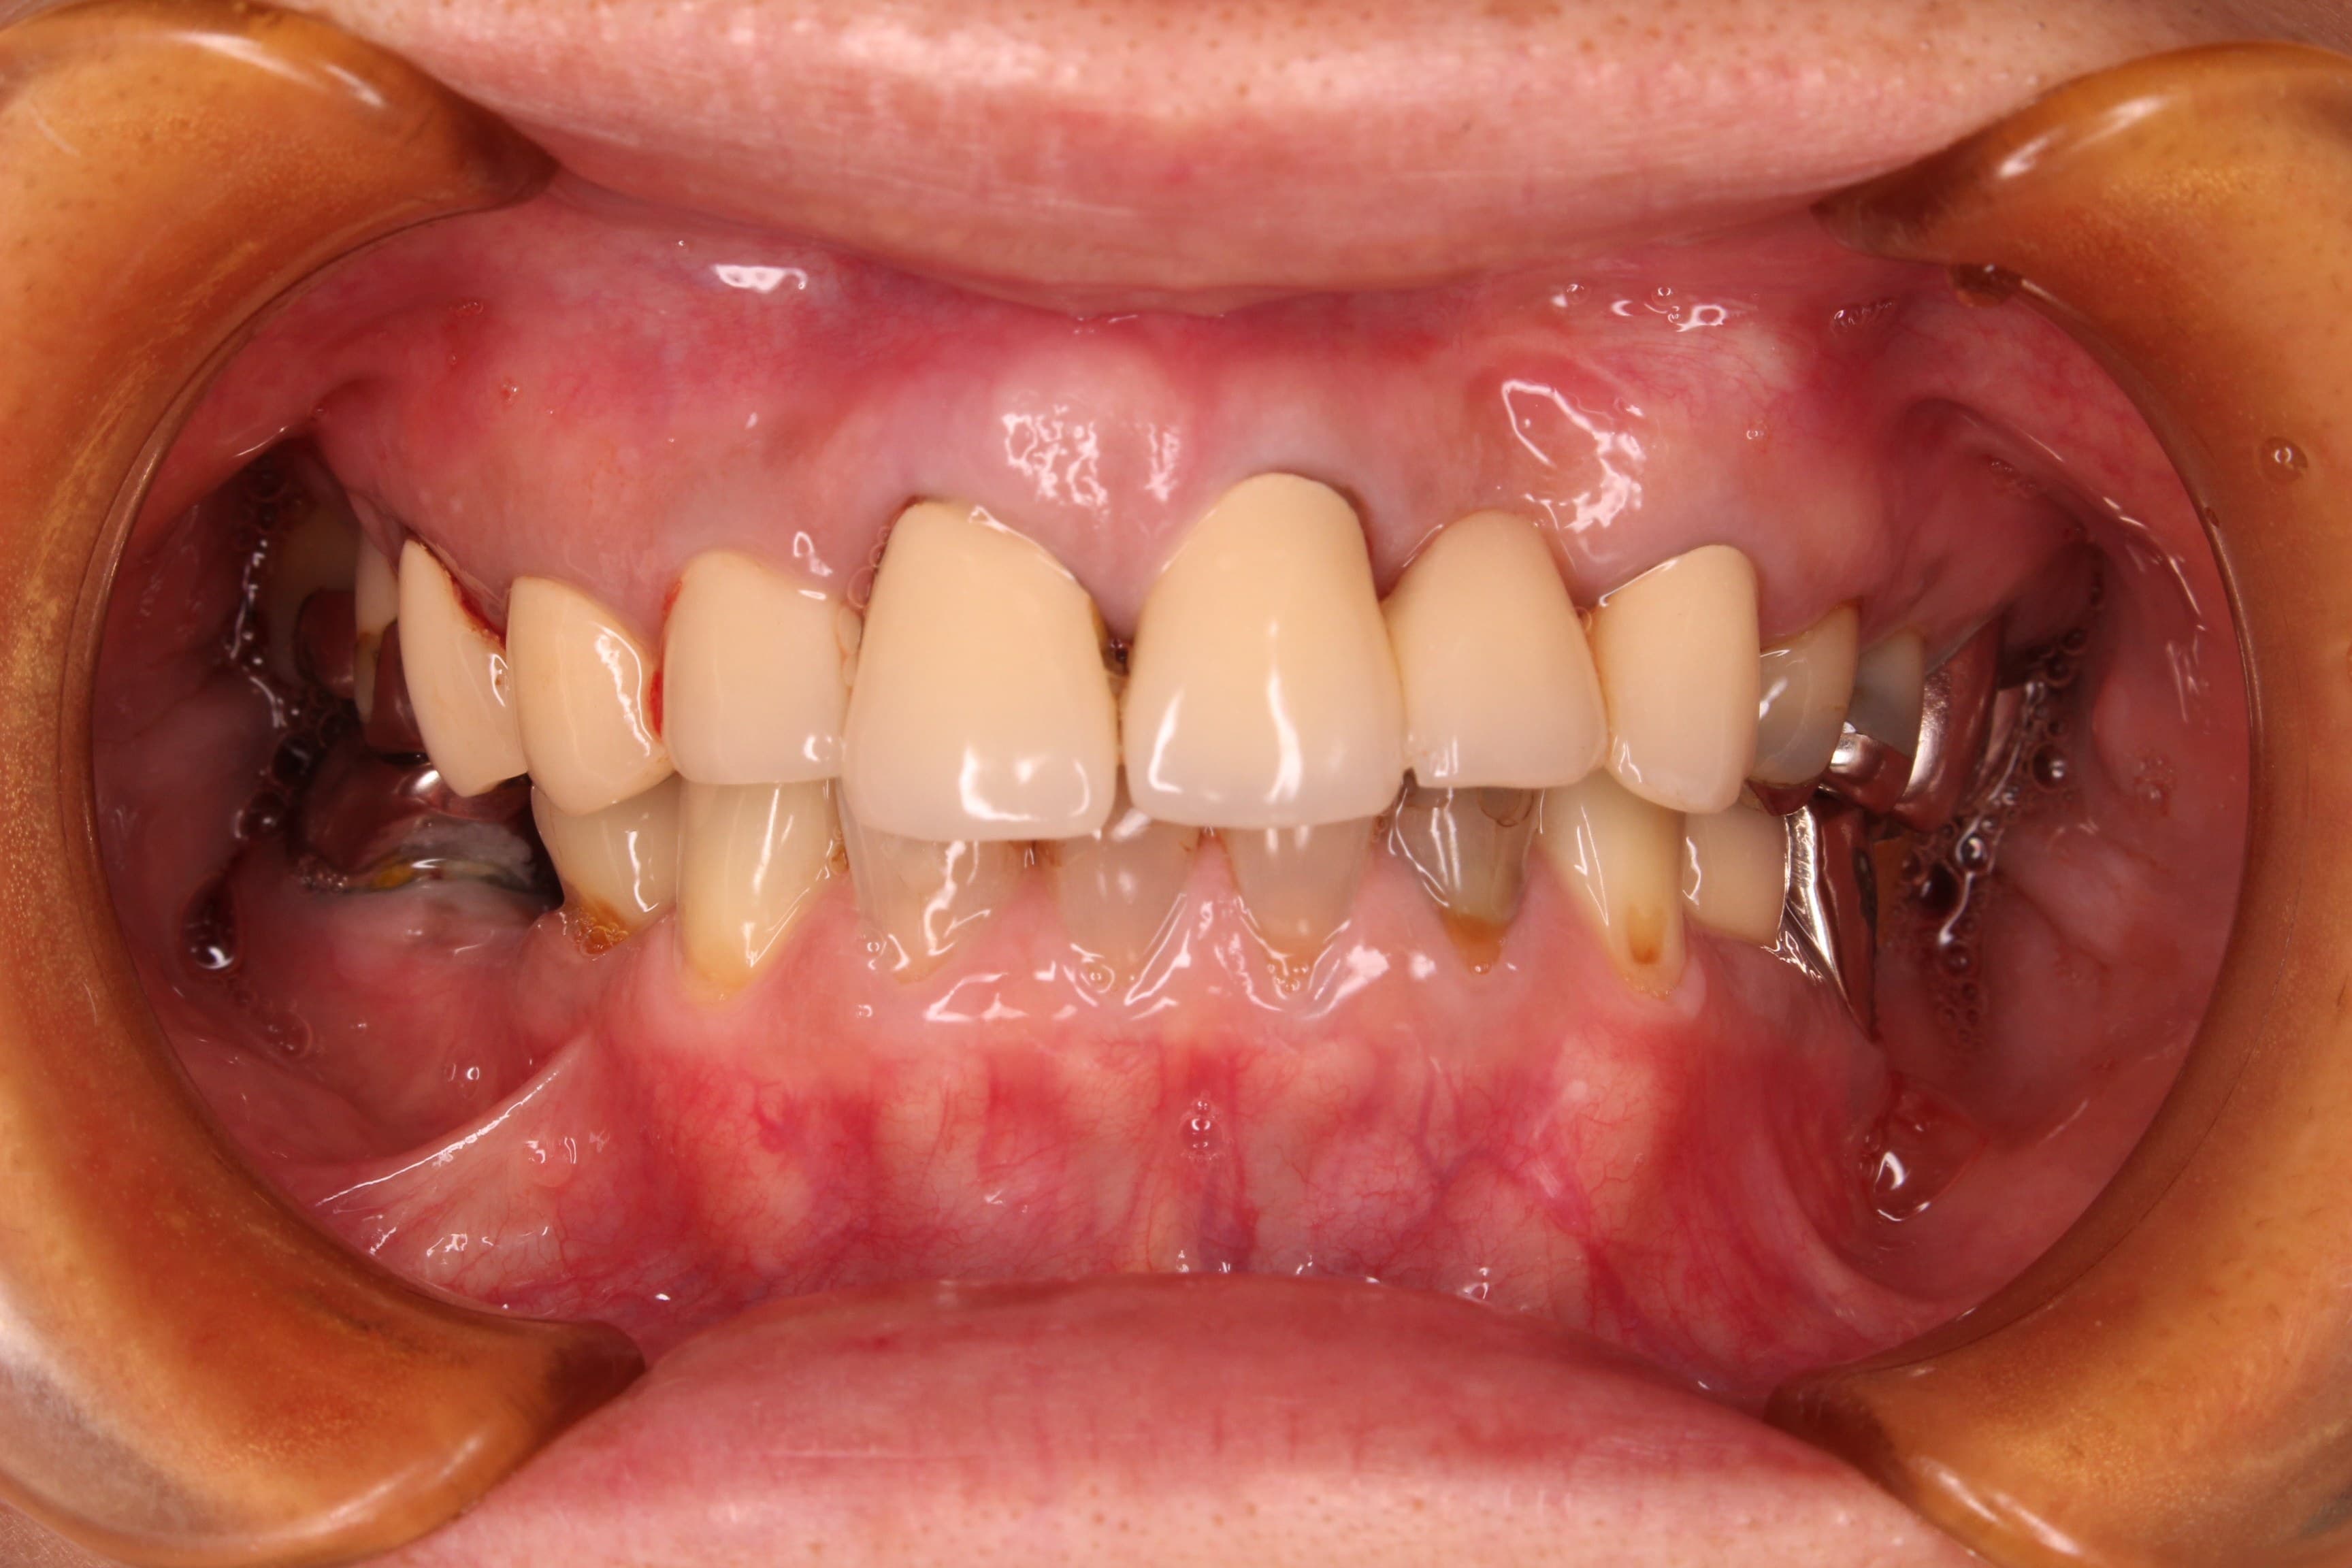

治療前

土台に使用していた歯の状態と、噛み合わにも問題があったのですが、非常に出血が多く、先ずは歯周病を改善する必要がありました。